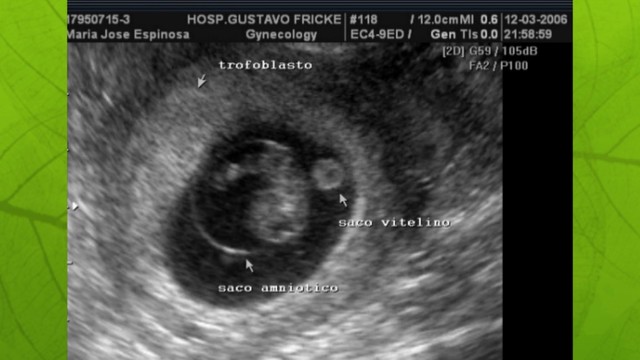

Implantación Union al endometrio en fase secretora reacción del endometrio compactacion de celula que acumulan glucógeno y lípidoscon la implantación el trofoblasto se diferencia capas interna citotrofoblasto límites célulares bien definidos externa sin Cícico trofoblasto sinlimites celular definidos nodo embrionario desarrolla capas embrion bilaminae ectodermo y endodermo.